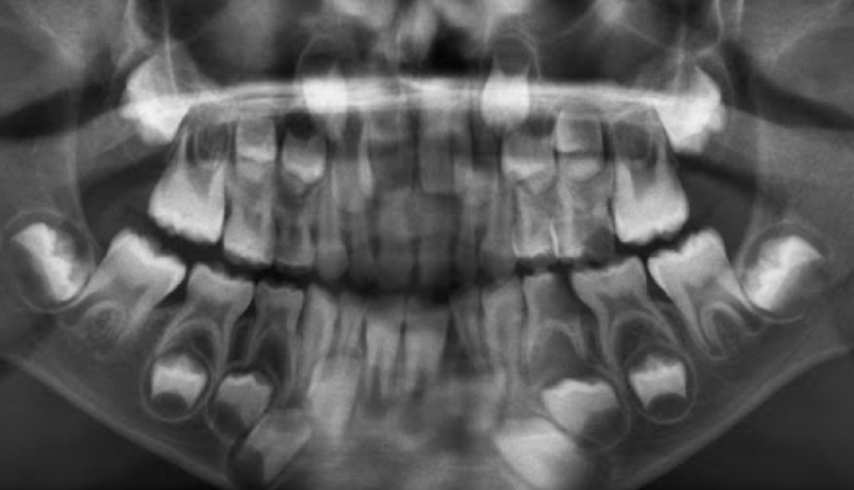

Permanent lower incisors present? Yes, so definitely 6-7

Permanent upper Incisors not erupted yet. Therefore not 7-8 y.o.

Conclusion = 6 y.o